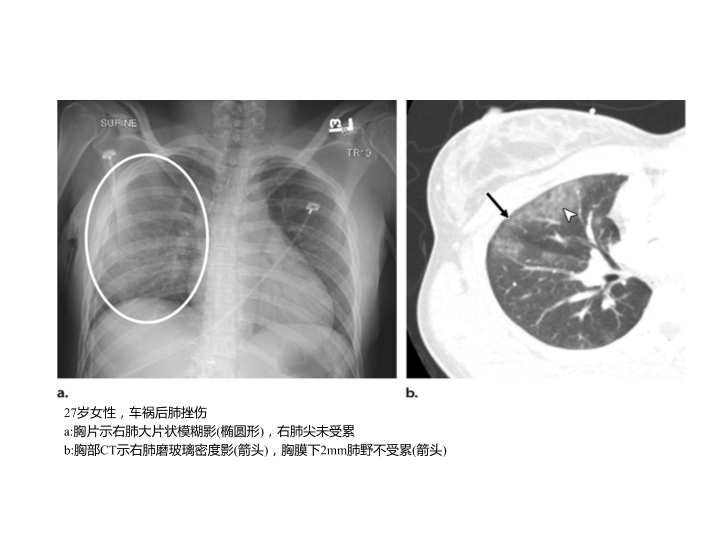

胸部外伤及胸腔积液处理